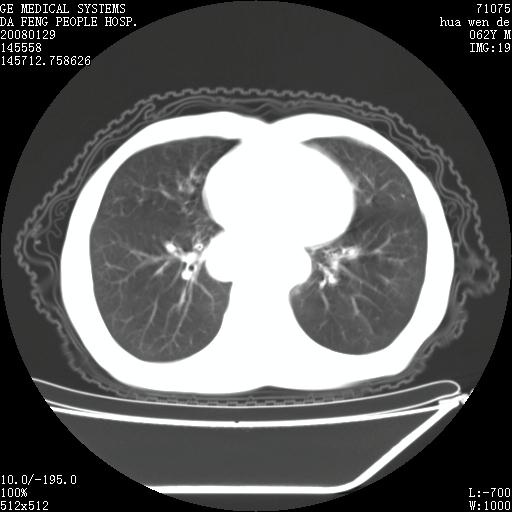

男性,67岁。作肺部检查时发现

理由:1、右上肺内病灶,空洞形成,有液平。

2、肺内多处炎症。

3、前段肺内炎症,支气管引流通畅,与肿块无关系。

1.整个食管扩张,未见明显占位性病变,贲门区亦未见明显占位病变,考虑:贲门失驰缓症;

2.右上肺病变边缘可见毛刺,囊壁厚度不均匀,周围境界较清楚,未见炎性渗出性影,右上肺外带可见片状影,边缘不清,考虑:肺癌伴空洞形成、右上肺炎。

食管全程扩张,壁均匀不厚,喷门失弛缓症

右上肺空洞可见液平,临近肺野磨玻璃密度,考虑1.结核2.脓肿